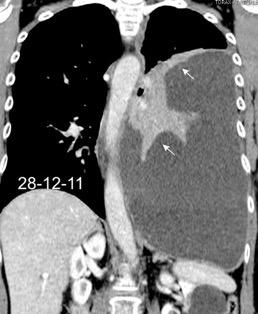

Pancreatitis. (lado izquierdo.68%)

Ortiz-Morales CM et al. Radiology of acute pancreatitis today: the Atlanta classification and the current role of imaging in its diagnosis and treatment . Radiologia (Engl Ed) . 2019

Dahnert 2017 Pancreatitis aguda